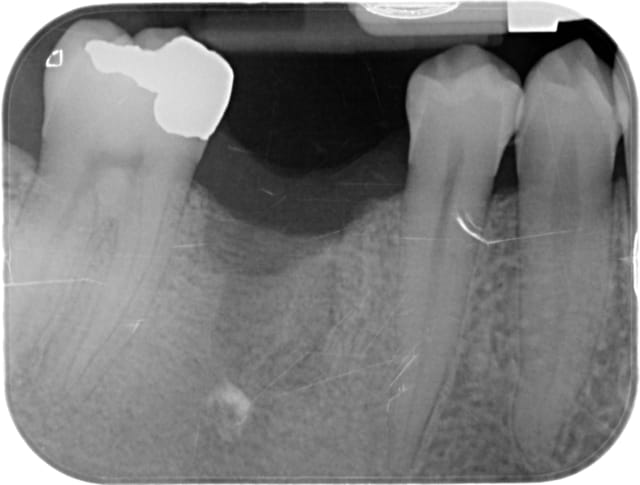

L'image de l'implant qui a cassé en apical, reprise quelques temps après avec une scie cloche, repose et radio à 5 ans.

Malgré une adaptation prothétique inadéquate, pas de gros problème.

Je précise qu'avant la "fracture" de l'implant, la résorption osseuse allait jusqu'à la partie cassée.

Ce qui est étonnant dans ce cas, c'est que le patient implanté dans les années 96, a perdu ses 3 ou 4 implants (je n'ai pas la fiche) pour cause de peri-implantite (ma première) et ce aussi bien sur du cylindrique que sur du Tatum D4 (20mmx 7 x 4.5)donc avec très gros dégâts à la dépose, et malgré ça le patient voulait du fixe, j'ai ré-implanté ( 6 implants) et plus aucun problème depuis ...

à le patient fumait... 2 à 3 cigarettes / jour et ne fume plus maintenant...